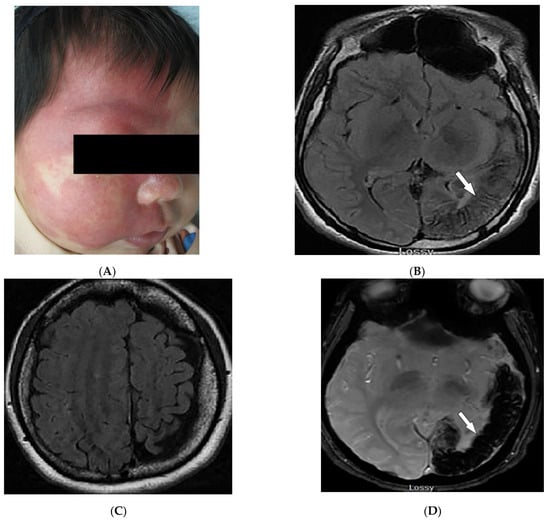

| PHACES syndrome | Craniofacial hemangiomas Posterior fossa malformations Cerebrovascular anomalies Eye anomalies | Ipsilateral cerebellar hemisphere dysplasia Major cerebral vessels dysplasia |

3.4. PHACES Syndrome